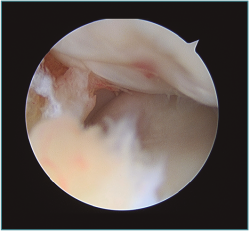

Figura 5. Imagen artroscópica de defecto condral en porción anteroinferior de capitellum. Óptica en portal anteromedial proximal.

Figura 6. Abundante sinovitis y cuerpo libre alojado en cámara anterior en un paciente con lesión osteocondral de tipo IV de la International Cartilage Repair Society (ICRS).